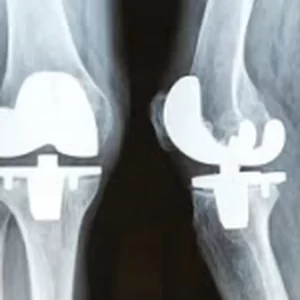

The Most Common Causes of Knee Pain

Knee pain is a common affliction, affecting nearly one in four adults and leading to discomfort and limited activity. Many different conditions and injuries can cause knee pain, and it’s important to determine what is causing it to determine how to best treat it. At Reflex Knee Specialists, we offer diagnosis and treatment services for